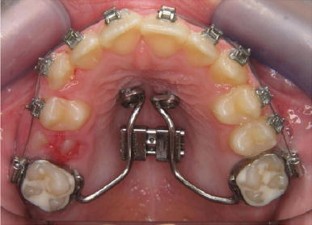

Fig. 4